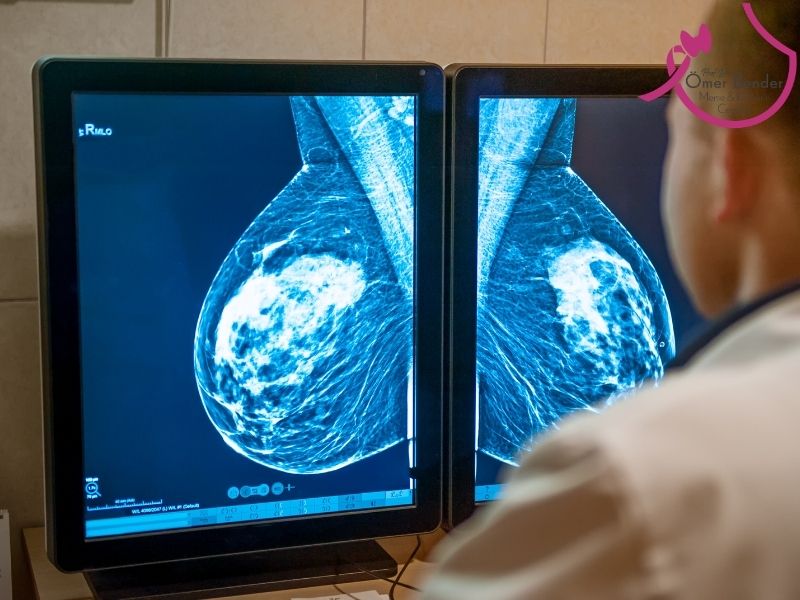

Meme kanserinin evrelenmesi, kanserin ne kadar yayıldığını ve ilerlediğini değerlendiren bir süreçtir. Meme kanserinin tedavisi, hastalığın içinde bulunduğu evreye (stage) göre planlanır. Evreleme için 3 temel faktör göz önüne alınır:

Evre 0, Duktal Karsinoma İn Situ safhasında tümör henüz kanalın dışına çıkmamıştır. Çevredeki yağ dokusuna, lenf bezlerine veya diğer organlara yayılmamıştır. Tümör daha oluşum göstermemiştir. Ancak görüntüleme yöntemleri aracılığı ile tanı konulur. Karsinoma in situ, kanser hücrelerinin meme kanallarında veya lobüllerinde başladığı ancak bu hücrelerin sınırlı bir alanda kaldığı bir durumdur. Meme kanserinin bu erken evresi, tedavi edildiğinde genellikle tamamen iyileştirilebilir. Tedavi edilmediği zaman ileri evrelere doğru geçiş başlayabilir.